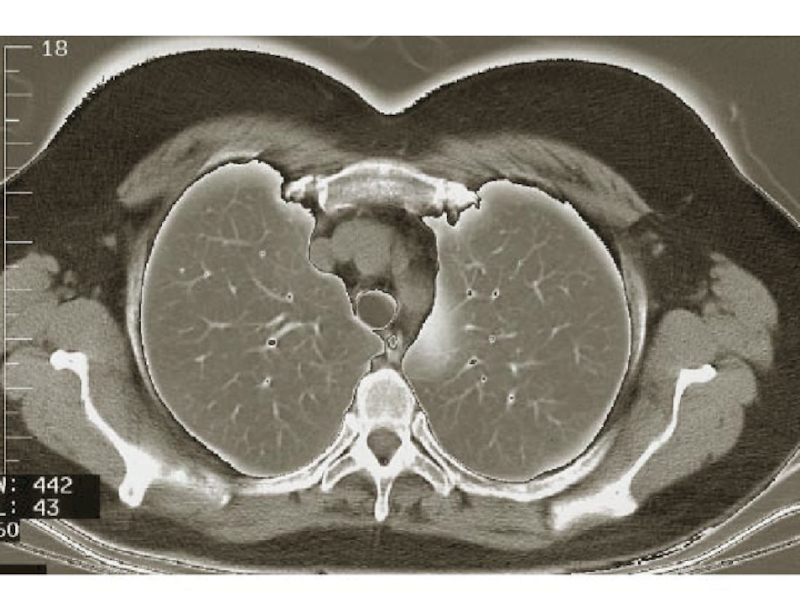

Слайд 87Томография и МРТ

Срез через верхнее средостение

Срез через нижнее средостение

Томография и МРТСрез через верхнее средостениеСрез через нижнее средостение